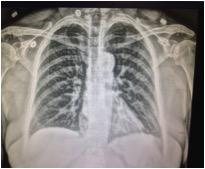

Technologists are also able to pull the patient’s information from the work list provided on the control panel, which is imported wirelessly to the hospital’s picture archiving and communication system (PACS), eliminating the potential for manual input errors. The advent of iterative reconstruction in imaging has made a huge impact for Maheu’s department as well, giving them the ability to provide physicians with additional detailed images without actually taking another X-ray and exposing the patient to radiation (see Figure 1).

Additional notable features include: S-Align, which provides precise alignment for superior imaging, as the angle of the detector is displayed on the THU to enhance image quality. A tube and line enhancement (TLE) function improves clarity of the images with a single onscreen click. “If you happen to be at the THU, you have the ability to see the image from there and don’t have to return to the console,” said Maheu. For line placement, he added, it is important to see PICC (peripherally inserted central catheter) lines or tubes — in the lung, for example. Further, a source-image distance (SID) guide supports multiple SID settings to aid in precise device positioning. Samsung’s imaging engine, S-Vue, delivers dependable and accurate diagnoses through advanced processing and adaptive filtering, providing enhanced image contrast and sharpness.